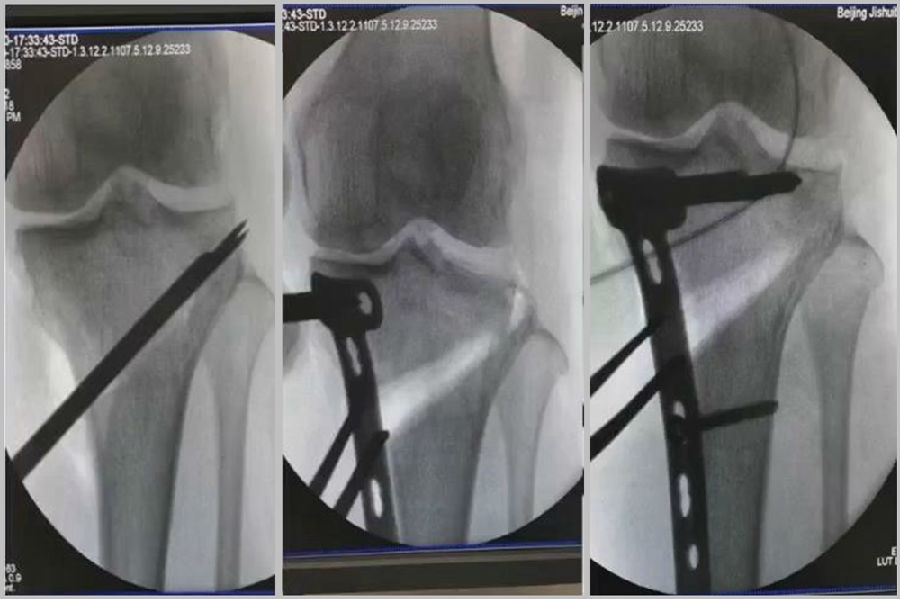

2、处理

(1)如果在手术台上,或是刚做完手术就发现矫正不良问题,此时比较简单。需要先跟患者进行沟通,在手术中直接将远端4颗螺钉卸下来,调整好力线后重新打入即可。但是注意要把远端单皮质螺钉换成双皮质螺钉。

(2)如果患者已经达到初始愈合,此时如果出现过度外翻,需要在内侧重新做内侧闭合楔。

(3)如果做完手术时间较长,出现过度矫正或矫正不足时,需要重新做力线分析,看一看力线在哪个方向可以再进行调整。胫骨侧有调整余地,就在胫骨侧进行调整;股骨侧需要调整,就在股骨侧进行调整。

3、总结

矫正不良与肢体位置、MCL浅层松解不够、力线验证及拉力螺钉加压过度有关。

要注意术前放置肢体于中立;MCL浅层彻底松解;外翻应力下验证力线;合理的拉力螺钉加压;及时处理发生的矫正不良。